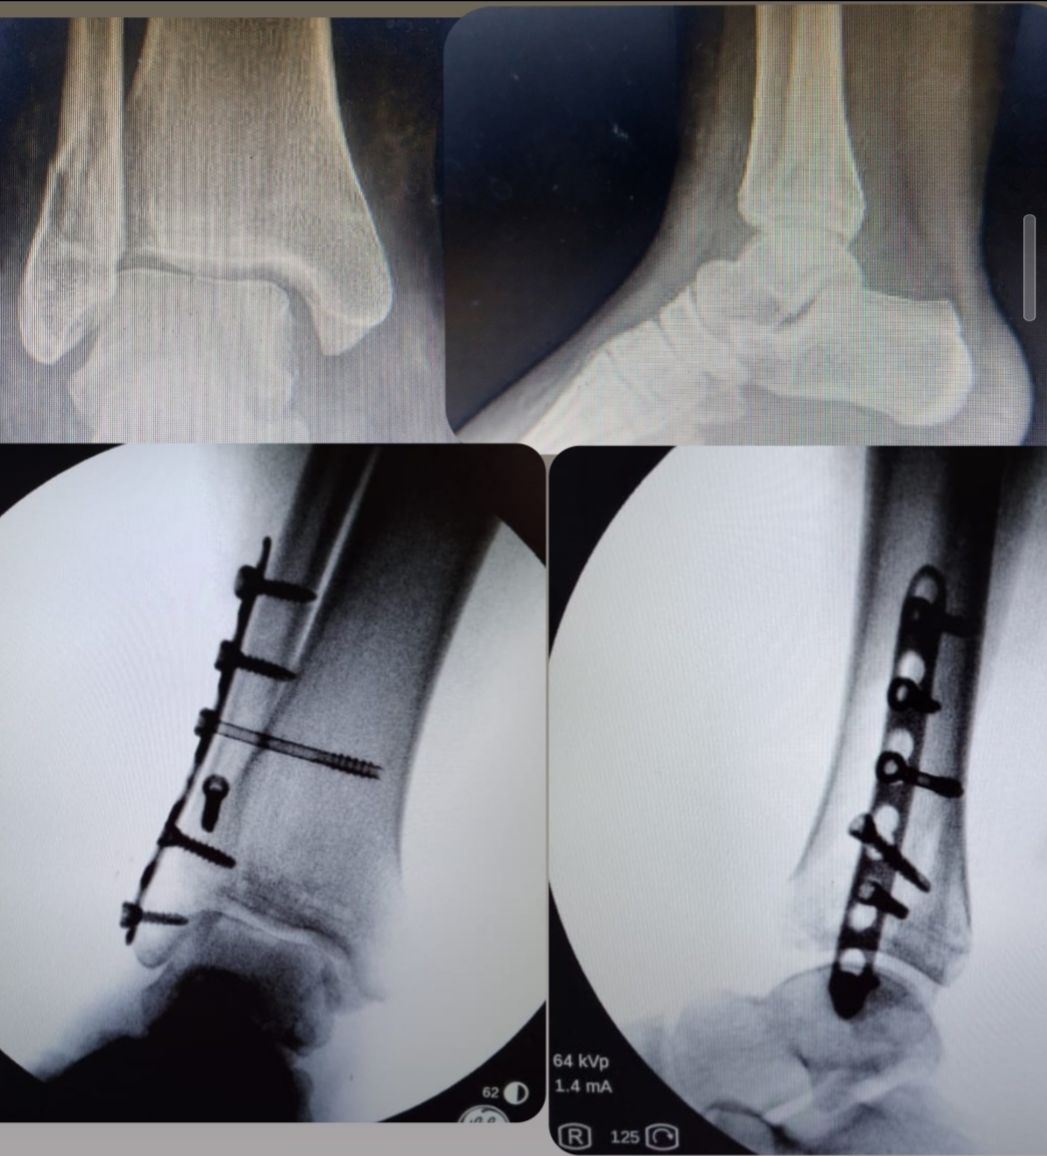

Las fracturas de pierna, pie y tobillo son lesiones frecuentes que pueden producirse por caídas, accidentes deportivos o traumatismos de mayor energía, y requieren una evaluación especializada para evitar secuelas funcionales. Según el tipo de fractura, su localización, el grado de desplazamiento y las características del paciente, el tratamiento varia. Se realiza una evaluación clínica e imagenológica completa para definir la conducta más adecuada en cada caso, que puede incluir manejo conservador con inmovilización o quirurgico de ser el caso. El objetivo es lograr una correcta consolidación ósea, aliviar el dolor y recuperar la función, priorizando una rehabilitación segura y progresiva.